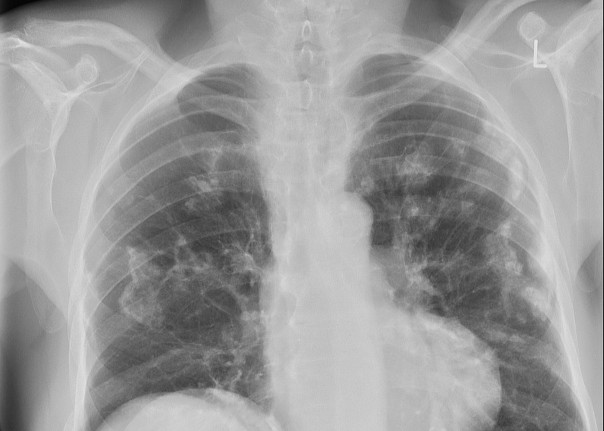

Untuk penanganan ARD, pasien akan menjalani wawancara medis, pemeriksaan, dan perawatan. Wawancara medis dilakukan untuk memastikan riwayat paparan asbes yang bersumber dari lingkungan kerja atau nonkerja. Pada tahap pemeriksaan, dokter akan melakukan tes radiologi serta tes fungsi paru pada pasien.

Pemeriksaan radiologi menggunakan Computed Tomography Scan (CT-Scan), High Resolution Computed Tomography (HRCT), atau ILO Radiograf. Untuk pasien yang dikonfirmasi mengalami paparan tetapi tidak menunjukkan adanya gejala, ILO Radiograf digunakan sebagai pemeriksaan awal.

“Jika sudah parah akan terlihat dengan ronsen biasa. Namun kalau masih dini, dengan ILO Radiograf. ILO Radiograf itu khusus untuk (pemeriksaan) penyakit karena debu-debu mineral, contohnya asbes, silika, dan batubara,” terang Ade.

Fibrosis yang terjadi di paru ini kemudian dikenal sebagai asbestosis. Kemunculan fibrosis juga menjadi penanda awal gejala ARD karena penurunan fungsi paru. Sedangkan serat asbes yang masuk ke selaput paru, dapat menyebabkan plak pleura hingga mesothelioma.